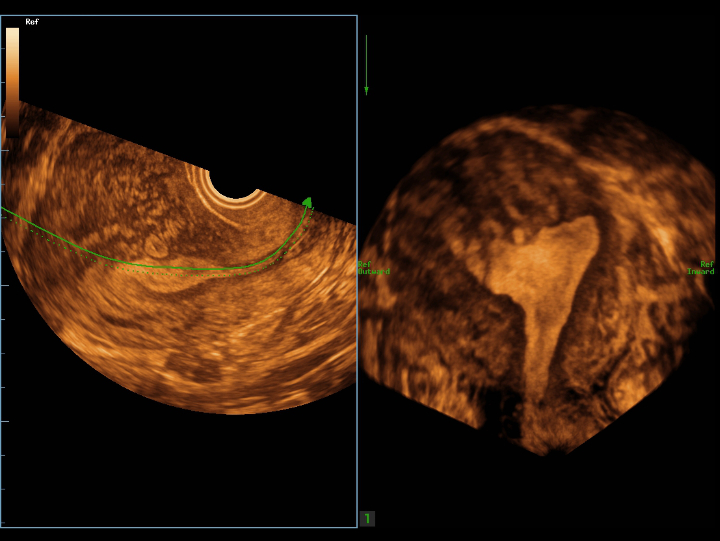

Pelvic ultrasound is considered as the first choice of imaging examination method to evaluate suspected gynecological diseases in women of all ages. Ultrasonography is usually the only necessary imaging examination to diagnose uterine, ovarian and adnexal diseases because of its wide availability, low cost and advantages of no ionizing radiation. With the development of volume ultrasound technology, 3D ultrasound has become a routine gynecological examination item. Through the acquisition of volume data, 3D ultrasound can display the uterus, cervix, ovary and uterine adnexa on any plane, and has more advantages in evaluating the uterine cavity.

UWN+ CEUS provides excellence contrast agent sensitivity and image penetration to get more diagnosis information for gynecology tumor or other difficult diseases. Also MindrayŌĆÖs STE (Sound Trouch Elastogtaphy) can quantitatively evaluate tissue stiffness which is helpful for previse diagnosis of difficult uterus, cervix and ovary diseases.